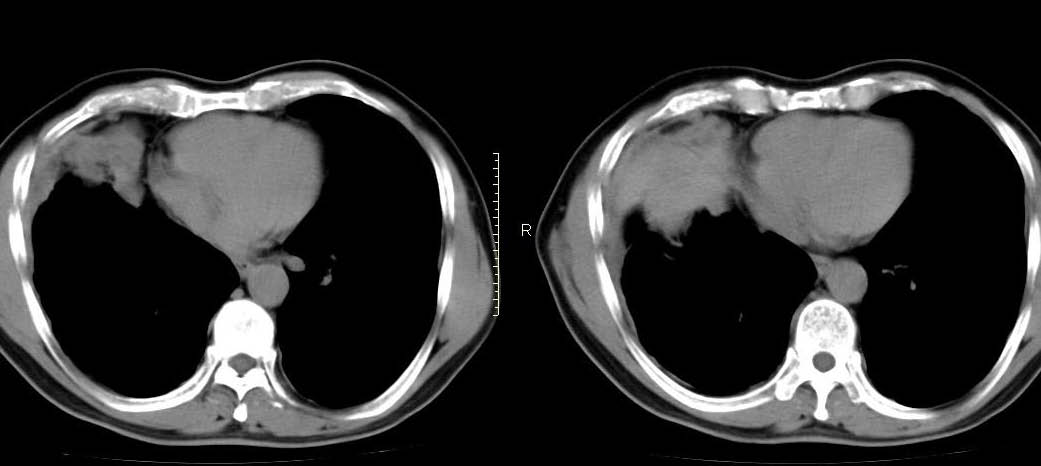

男,56岁,右侧腋窝下巨大软组织包块转移。欢迎讨论。

该病例为已经确诊的右侧恶性胸膜间皮瘤病例,有青石棉接触史,早期就是胸水,右侧胸壁“花边状改变”,心隔角区软组织阴影形成。近期右侧腋窝下巨大软组织包块,病检为转移瘤。图片没有完全考来,主要是给大家看一下胸膜间皮瘤的病例。,右侧

右肺下叶节段性肺不张、右侧胸膜肥厚并包裹性积液。“右侧腋窝下巨大软组织包块转移?”就目前图片看,没见!请上传完整图像。